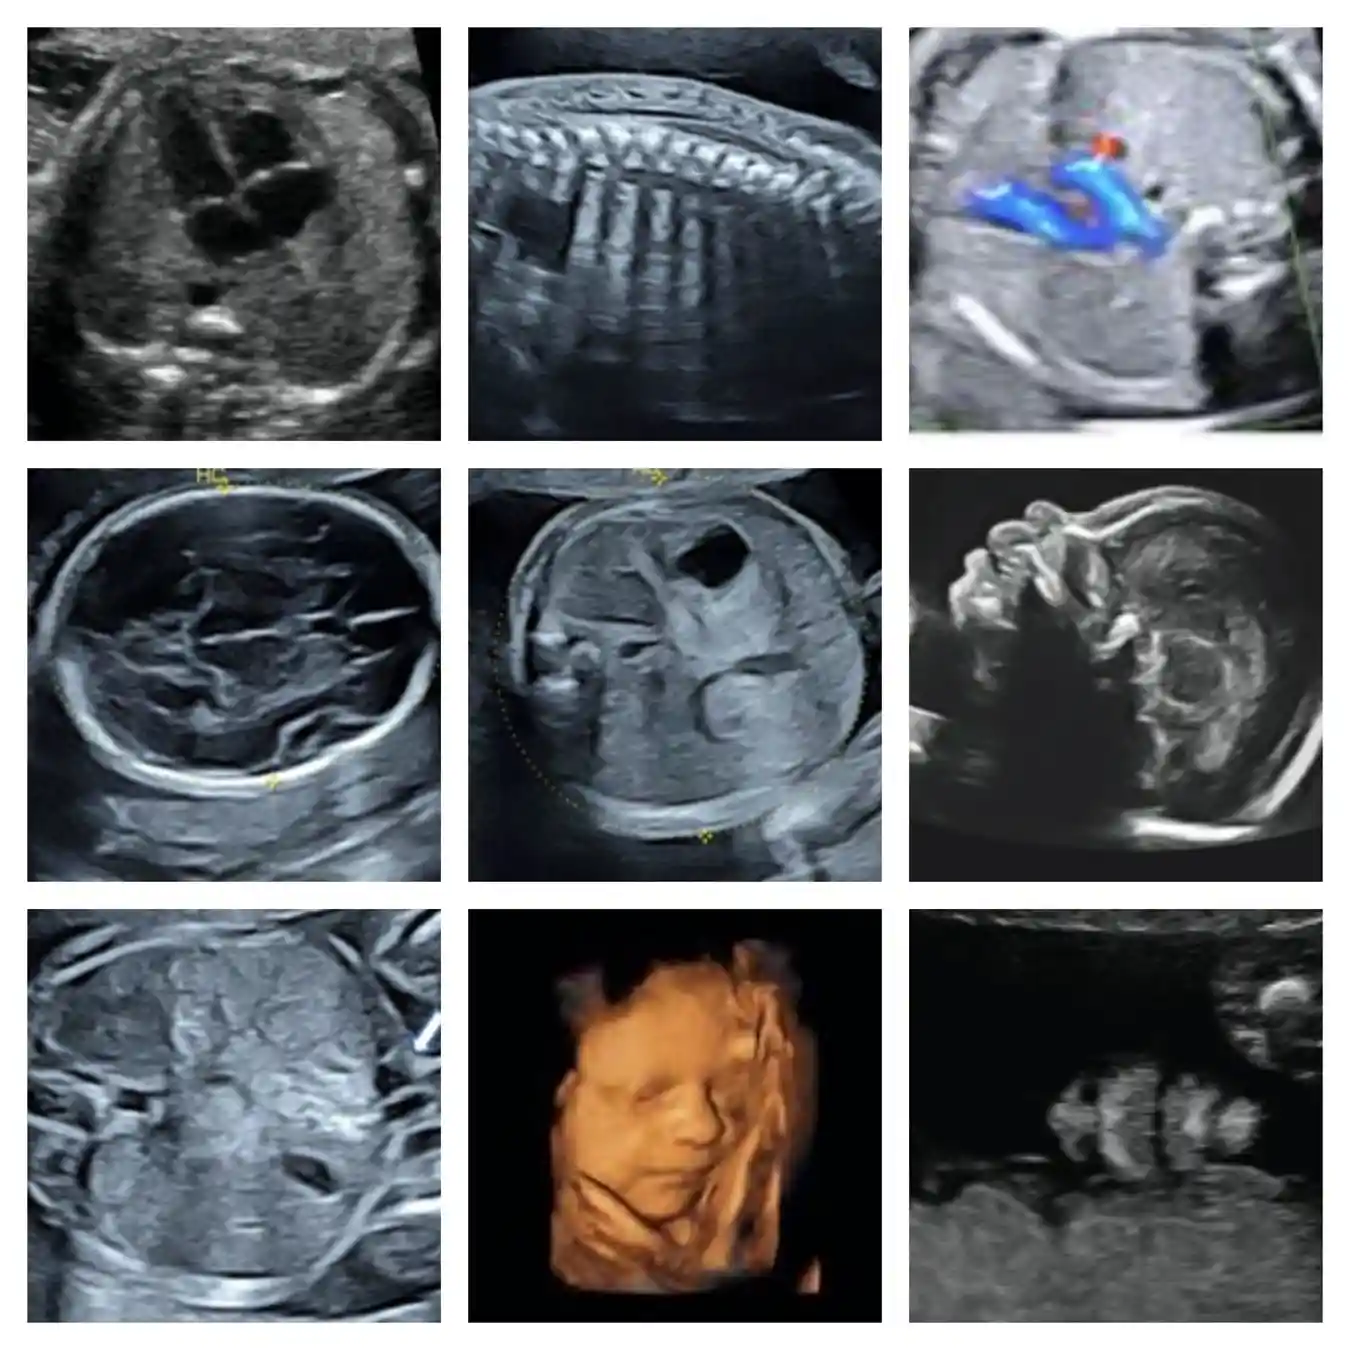

• ❤ Se realiza la evaluación estructural anatómica del feto de manera detallada, permite identificar que se hayan formado adecuadamente todos los órganos del bebé, permite detectar alteraciones o defectos estructurales.

• ❤ Se lleva a cabo la evaluación del riesgo de parto pretérmino a través de la evaluación ultrasonográfica vía vaginal de la longitud del cuello uterino.

• ❤ Evaluación de la localización placentaria por vía vaginal, ayuda a descartar placentas de inserción baja o placentas previas (cuando se insertan a nivel del cuello uterino).

• ❤ ¡Conocerás el sexo de tu bebé!

Todas las pacientes embarazadas deben realizarse este ultrasonido entre la semana 18-24 de gestación y solo deberá ser realizado por un médico especializado y altamente capacitado, como un médico materno fetal.